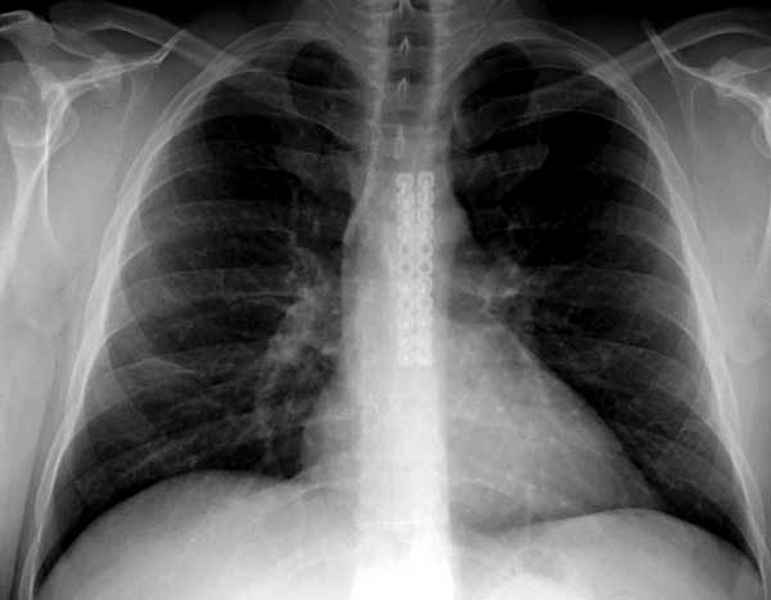

А простые посттравматические ложные суставы грудины приходилось

оперировать с ограничителем сверла и с фиксацией 2.4 мм пластинами с

угловой стабильностью.

Вложение не в текстовом формате было извлечено…

Имя     : sternum ap.jpg

Тип     : image/jpeg

Размер  : 30465 байтов

Описание: отсутствует

Url     : http://weborto.net:8080/pipermail/ortho/attachments/20090403/0de56d8e/attachment-0014.jpg